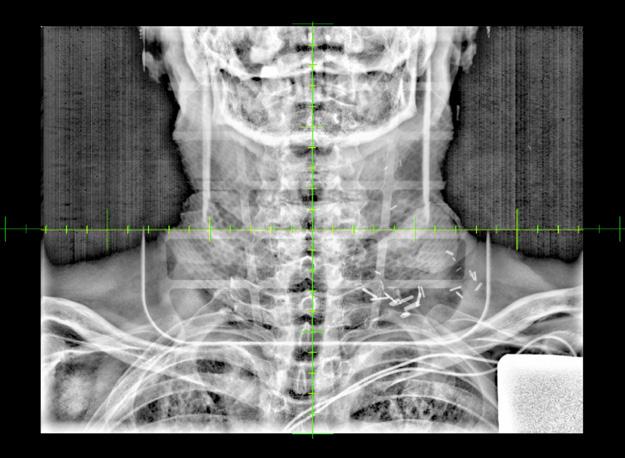

Électrophysiologie médicale

Tétralogie de Fallot : combinaison de quatre anomalies cardiaques congénitales

La tétralogie de Fallot est la plus fréquente des cardiopathies congénitales cyanogènes, représentant près de 8 % d’entre elles. Cette malformation tire son nom d’Étienne-Louis Arthur Fallot, qui l’a décrite en 1888.

La tétralogie de Fallot se caractérise par quatre anomalies distinctes, comme ÉtienneLouis Fallot, anatomopathologiste, les avait observées lors d’autopsies. En réalité, deux de ces anomalies suffisent à expliquer la physiopathologie de cette malformation, les deux autres n’étant que des conséquences. Cette introduction vise à offrir un aperçu des caractéristiques cliniques, des défis diagnostiques et des approches thérapeutiques actuelles de cette pathologie (figure 1 ).

Anomalies anatomiques de la tétralogie de Fallot :

■ Rétrécissement de l’artère pulmonaire.

■ Hypertrophie du ventricule droit, qui compense la pression exercée par le rétrécissement de l’artère pulmonaire.

■ Communication interventriculaire entre les ventricules droit et gauche.

■ Malposition de l’aorte à droite, chevauchant le septum interventriculaire. Ce déplacement partiel au-dessus du ventricule droit résulte du défaut d’alignement à l’origine de la communication interventriculaire.

Cœur normal Tétralogie de Fallot

Dextroposition de l’aorte Sténose pulmonaire

Communication inter-ventriculaire

Hypertrophie ventriculaire droite

Figure 1 : Différence entre un cœur normal et un cœur ayant une malformation appelé la tétralogie de Fallot.

Anomalies principales :

■ Sténose (rétrécissement) de la voie d’éjection du ventricule droit : Cette sténose peut se situer au niveau de l’infundibulum pulmonaire, de l’anneau pulmonaire ou du tronc de l’artère pulmonaire (avant la bifurcation en deux artères pulmonaires). Le rétrécissement peut être localisé ou prédominer sur une de ces trois parties dans les formes mineures. En revanche, dans les formes sévères, il peut s’étendre à l’artère pulmonaire, y compris aux branches droite ou gauche.

■ Communication interventriculaire (CIV) : Cette communication se situe près de l’origine des gros vaisseaux, notamment de l’aorte. Elle résulte d’un mauvais alignement entre l’aorte et la portion musculaire du septum interventriculaire.

Ces caractéristiques anatomiques et physiopathologiques permettent de comprendre la complexité et la gravité de la tétralogie de Fallot, nécessitant une prise en charge médicale spécialisée.